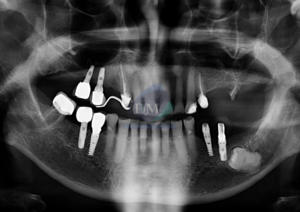

Caso 300 – IDM – HIPERPLASIA DE APÓFISIS CORONOIDES DE LADO DERECHO – IDM

Paciente femenino de 16 años acude al Instituto de Diagnóstico Maxilofacial (sede Miraflores) para evaluación quirúrgica. Radiografia Panorámica A la evaluación de la radiografía panorámica